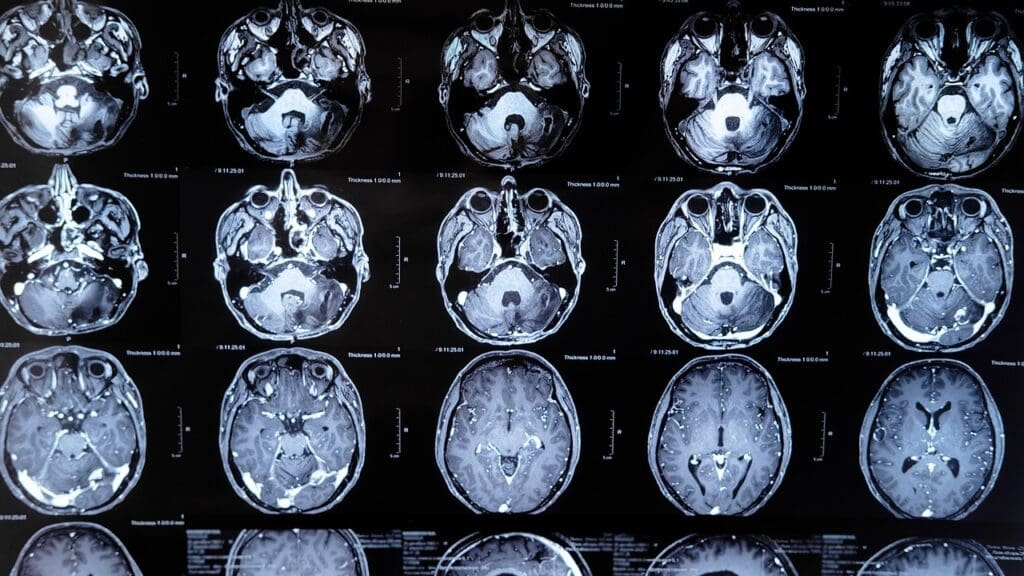

Diagnostic Approaches and Timeline

Doctors use MRI and CT scans to find brain tumors in kids. Sometimes, they take a biopsy. The time it takes to get a diagnosis can vary. But, quick diagnosis is key to start treatment.